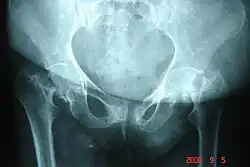

Potentiell von einer Osteoradionekrose gefährdet sind die Knochen, die in der unmittelbaren Nähe des Zielorgans der Strahlentherapie liegen. So kann beispielsweise eine Radiatio eines Nierenzellkarzinoms zu einer Osteoradionekrose der Lendenwirbel führen. Bei gynäkologischen Tumoren sind die Beckenknochen, bei Kopf-Hals-Tumoren beispielsweise der Unter- oder Oberkiefer, bei Brustkrebs die Rippen und Knochen des Schultergürtels gefährdet.[2]

Osteoradionekrosen lassen sich röntgenologisch als unscharf begrenzte dichte Knochentrümmer gut erkennen. Dadurch können sie von Knochenmetastasen unterschieden werden. Bei gemischt osteoplastischen/osteolytischen Knochenmetastasen ist die Differentialdiagnose deutlich schwieriger.[2] Eine Knochenszintigraphie kann hier zur Klärung des Befundes beitragen. Maximale Diagnosesicherheit bietet eine Knochenbiopsie.[2]